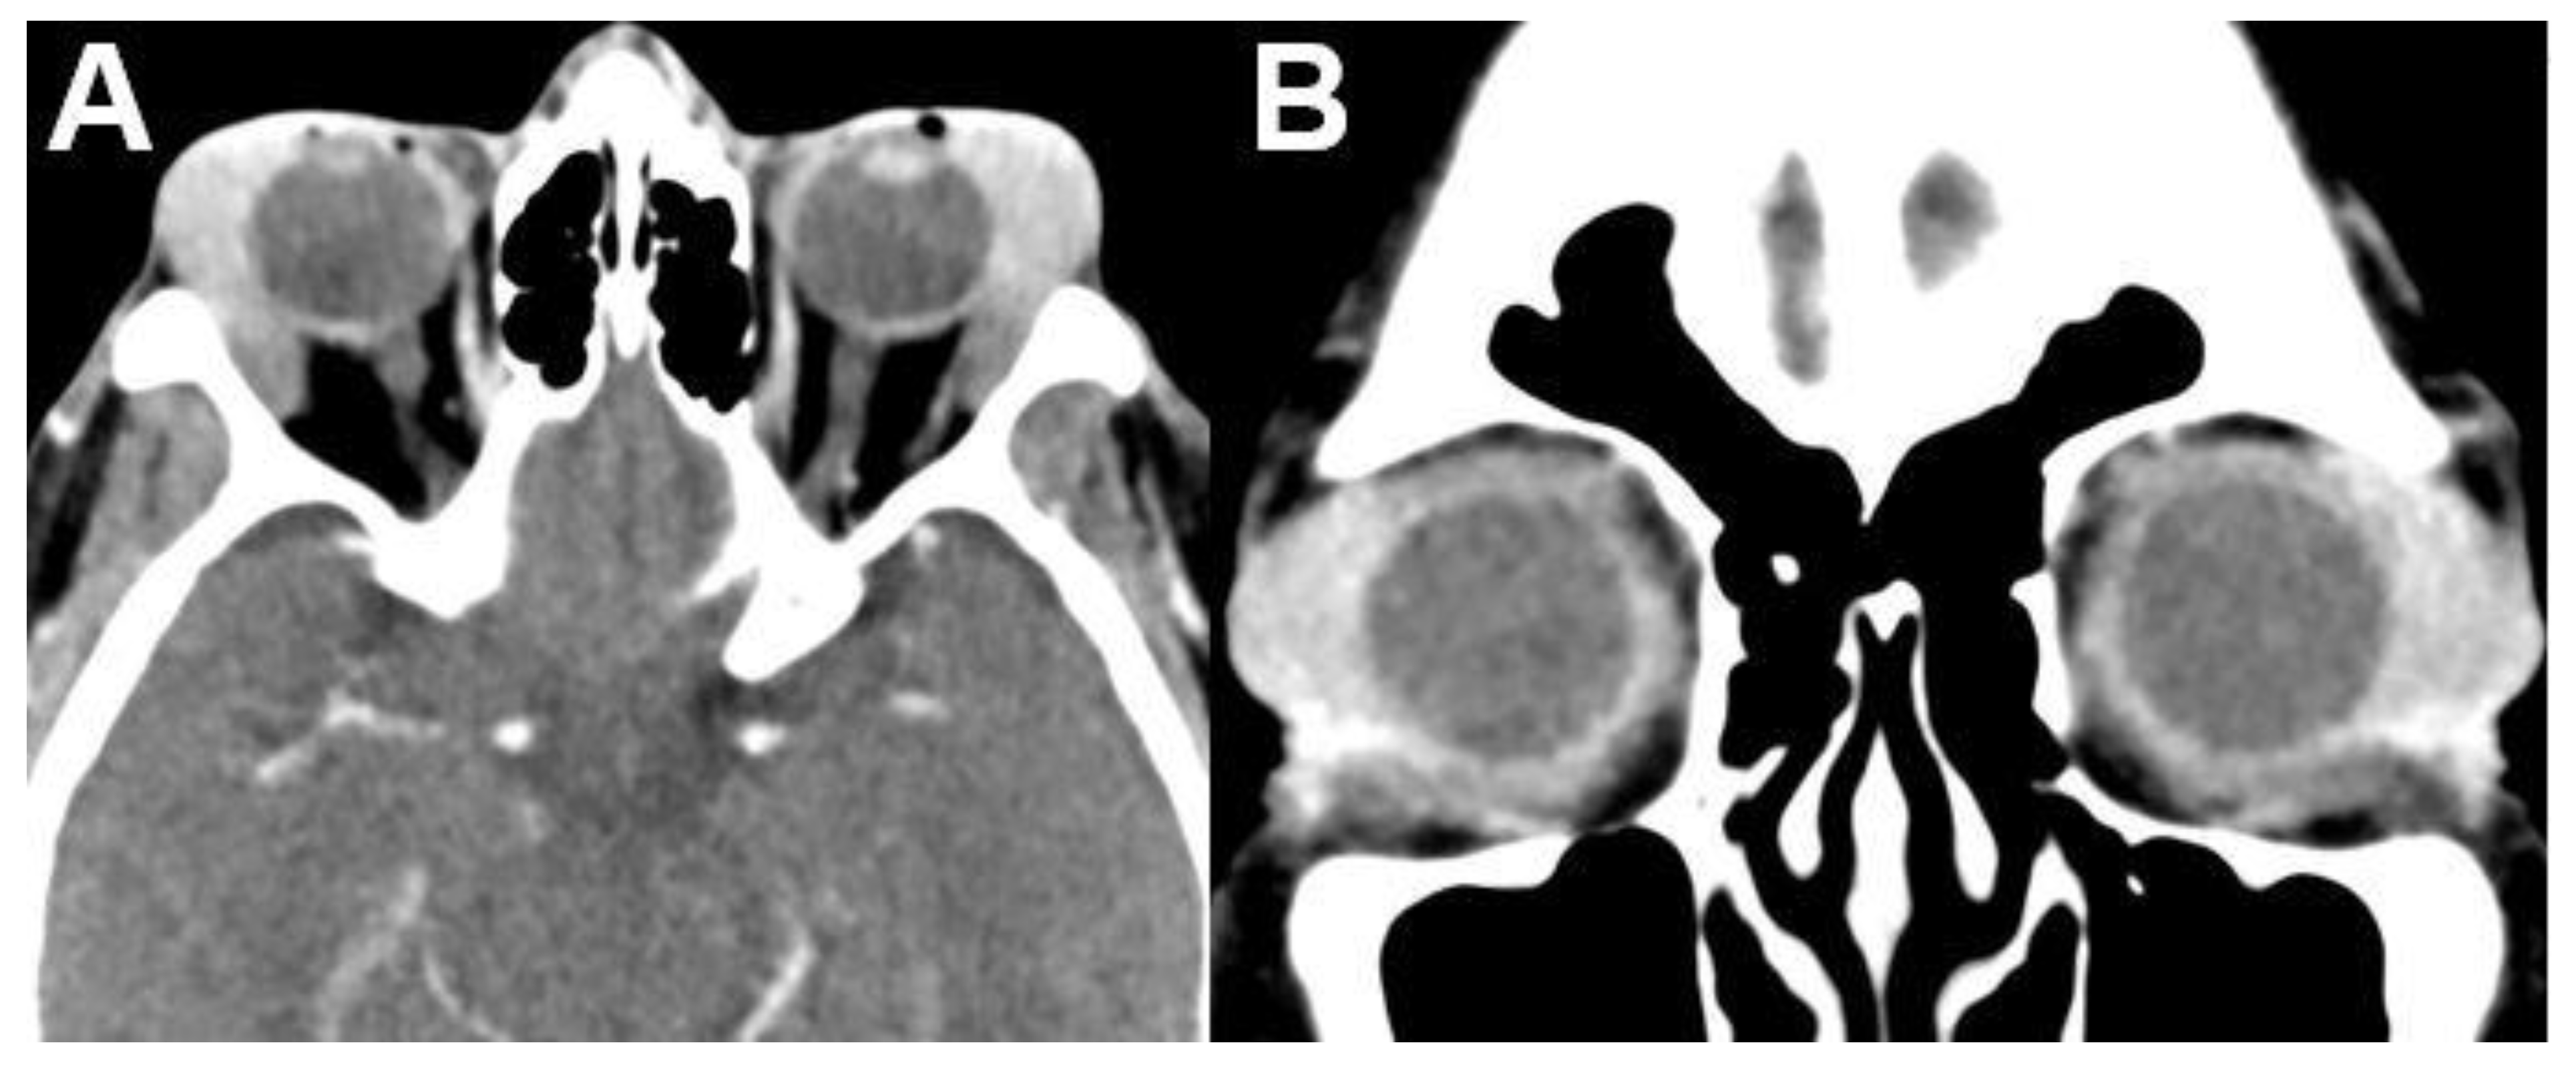

3.1.2. Uveal Melanoma